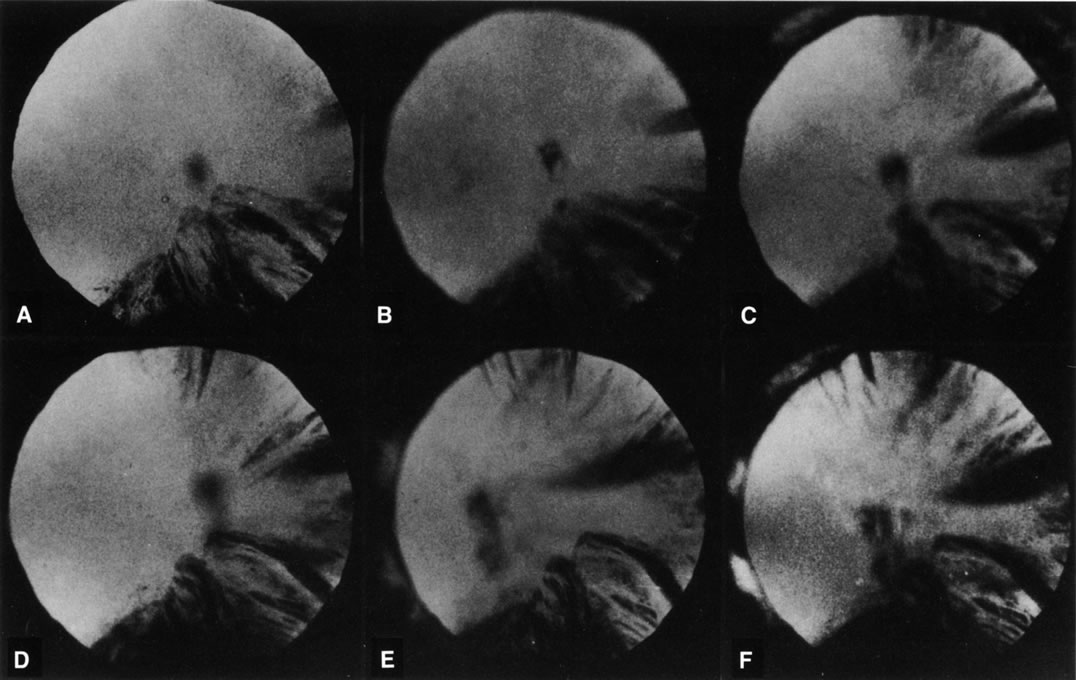

Fig. 8. Follow-up retroillumination photographs of an eye with a cortical

cataract, obtained at various intervals. A. First visit (1-21-87); B. 1 year later (1-27-88); C. 22 months later (11-14-88); D. 28 months later (12-4-89); E. 35 months later; F. 41 months later (6-18-90). With such photographs

one may be able to plot the progression rate of a cortical cataract, and

aid in performing longitudinal studies. Note the central opacity, which

is out of focus and represents a small posterior subcapsular

cataract.

Fig. 8. Follow-up retroillumination photographs of an eye with a cortical

cataract, obtained at various intervals. A. First visit (1-21-87); B. 1 year later (1-27-88); C. 22 months later (11-14-88); D. 28 months later (12-4-89); E. 35 months later; F. 41 months later (6-18-90). With such photographs

one may be able to plot the progression rate of a cortical cataract, and

aid in performing longitudinal studies. Note the central opacity, which

is out of focus and represents a small posterior subcapsular

cataract.